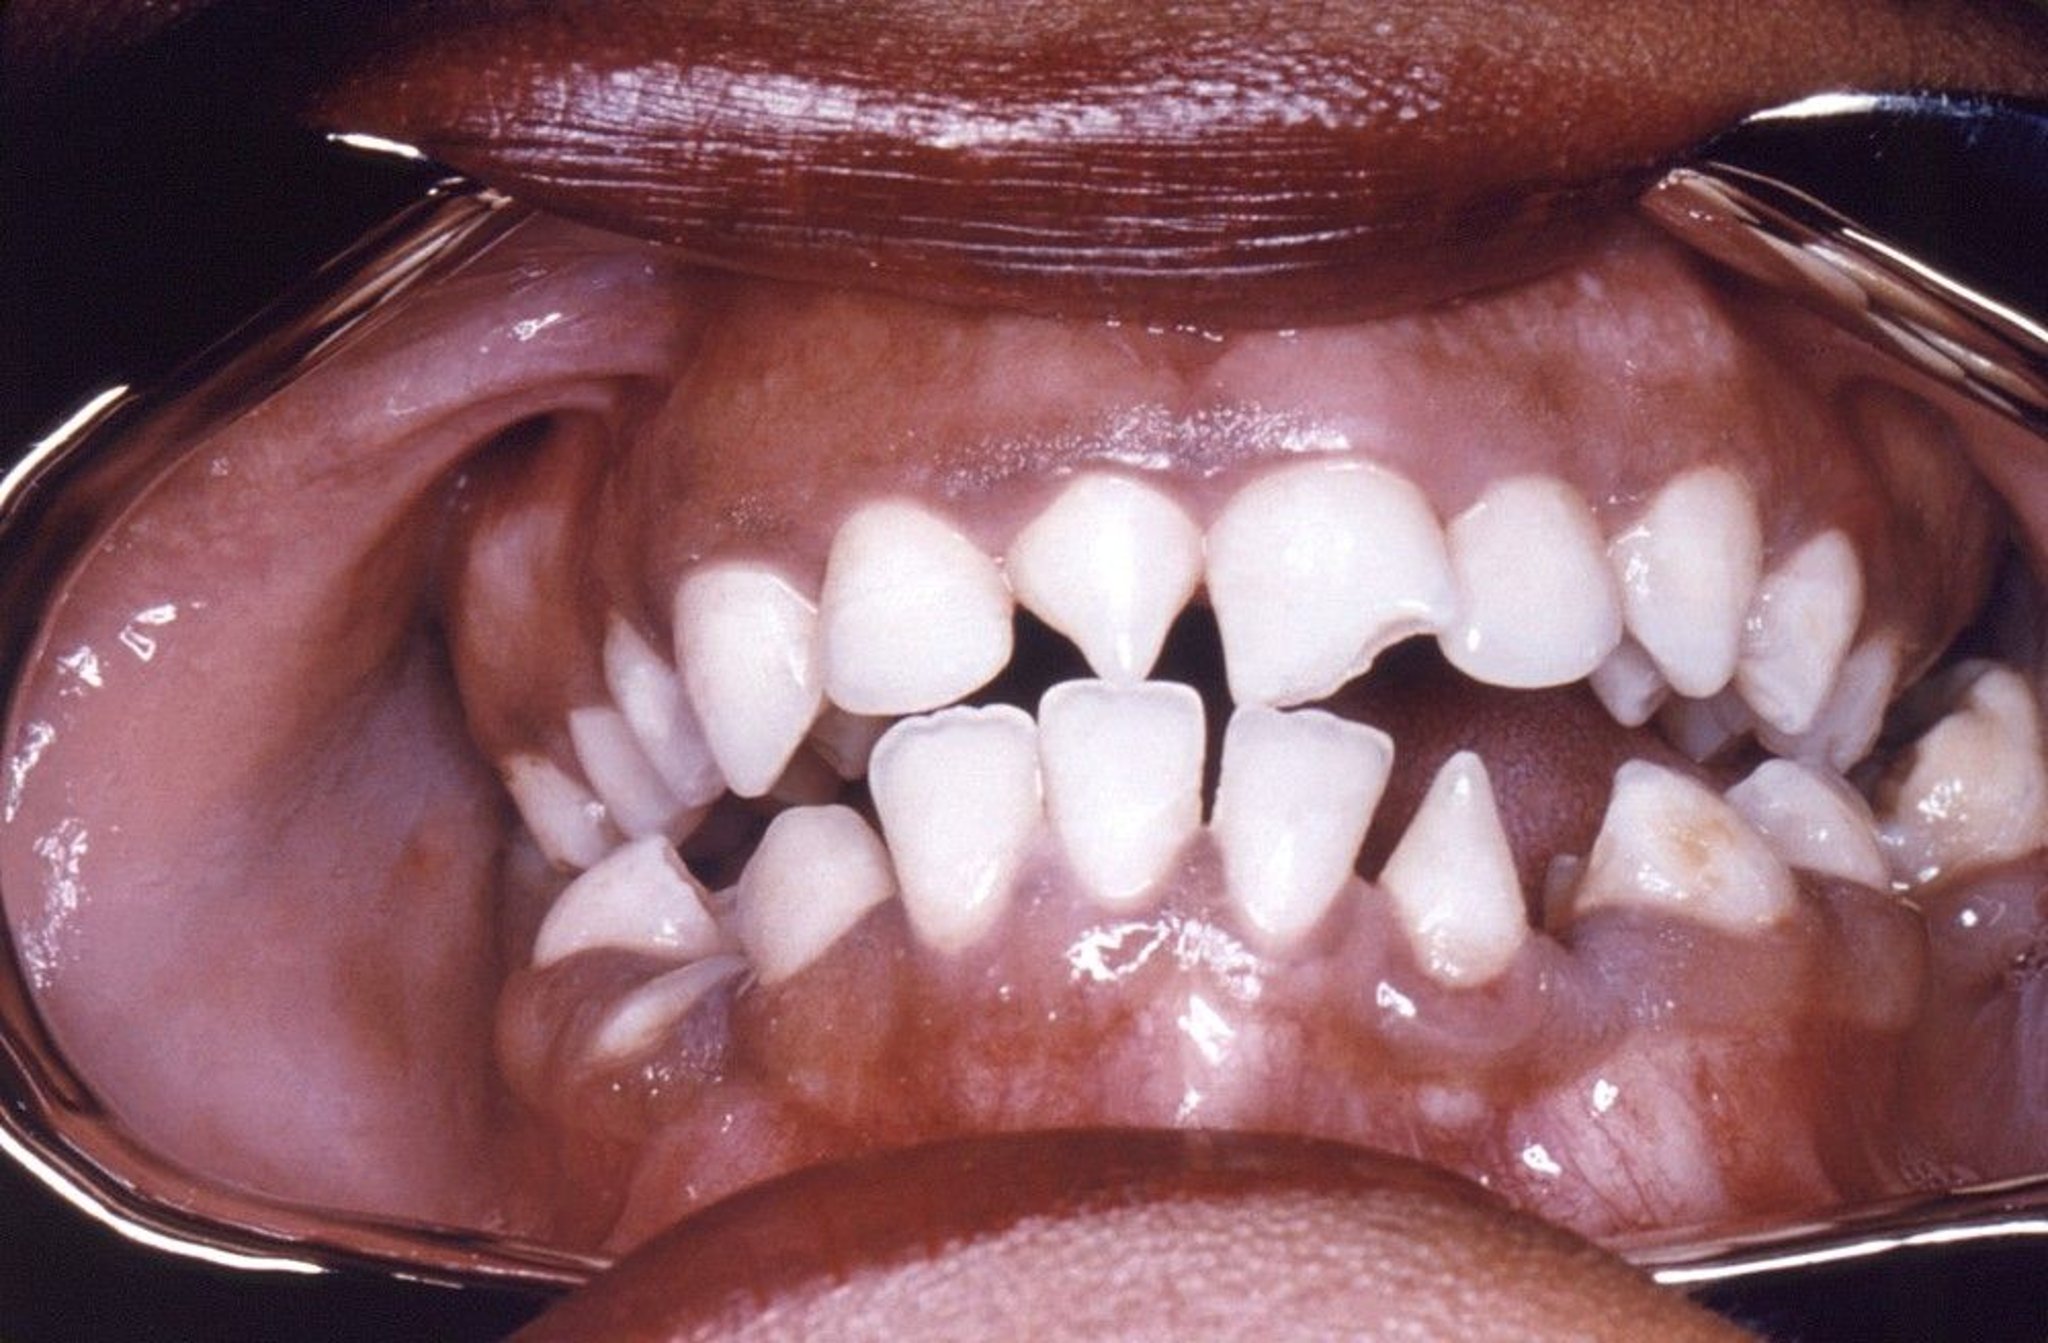

Hutchinson Incisors

This photo shows triangular shaped deformity of right upper and left lower incisors caused by congenital syphilis.

Image courtesy of Robert E. Sumpter via the Public Health Image Library of the Centers for Disease Control and Prevention.